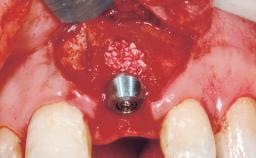

Immediate Flapless Placement of an Implant in a Maxillary Right Lateral Incisor Site

This 43-year-old male patient, a non-smoker, came to our practice because of a fracture of tooth 12 caused by a bicycle accident. Due to the combined para- and infrabony crown and root fracture, tooth extraction, and subsequent implant placement were suggested to the patient as the therapy of choice. The patient had high esthetic expectations with regard to the treatment outcome and asked for an immediate fixed provisional restoration. His individual esthetic risk profile summed up to a medium esthetic risk.

| Placement Protocol | Immediate implant placement |

| Tooth Site | Maxillary incisor or canine |

| Socket Morphology | Single-root socket |

| Socket Integrity | Sufficient, with intact bone walls |

| Bone Volume | Sufficient, with intact walls |